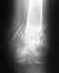

Здравствуйте, в 1994 и 2004 были переломы лодыжек (катание на коньках и лыжах) в 2014 году началась боль (травмы не было) при ходьбе ходил к травматологу сказал артроз лечил физиотерапией но боль никуда не девалась

в августе 2015 не смог наступить на ногу (травмы не было) пошел к травматологу сделали снимок он сказал перелом внутренней лодыжки гипс 1,5 месяца после снятия гипса разрабатывал ногу потом опять боль (травмы не было) сделали снимок сказал перелом разошелся хотел наложить гипс я отказался и сделал кт (20.11.15) сделал три скрина на свое усмотрение Обязательно ли операция (или возможно консервативное лечение) и правда ли это переломhttp://s019.radikal.ru/i644/1511/3a/6ab21e9eed50.jpghttp://s019.radikal.ru/i637/1511/3d/a58dc08666d5.jpghttp://s019.radikal.ru/i621/1511/2e/f27cfefd2594.jpgВ май 2014 была большая нагрузка на голеностоп тащил волоком трубу на даче после этого все началось Вот снимки (при первом посещении травматолога 31.08.15, после снятия гипса 15.10.15, и когда снова разошелся перелом со слов травматолога 19.11.15)b и снимок май 2014снимки 31.08http://s017.radikal.ru/i406/1511/b1/6fab7da5fc08.jpghttp://s017.radikal.ru/i404/1511/cd/5a28b48f7d89.jpgснимки 15.10http://s016.radikal.ru/i336/1511/16/43934cd377e0.jpghttp://i004.radikal.ru/1511/2f/0b8f5962e3f8.jpgснимки 19.11http://s017.radikal.ru/i439/1511/9d/e7f0a31c6da1.jpghttp://s019.radikal.ru/i615/1511/d6/89861733c5dd.jpgЕще снимок май 2014 г когда все началосьhttp://s49.radikal.ru/i124/1512/68/a6623d00923d.jpg